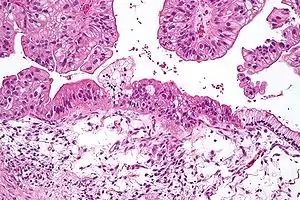

| 苏木精-伊红染色下的黏液性卵巢上皮癌組織 (顯微照相) | |